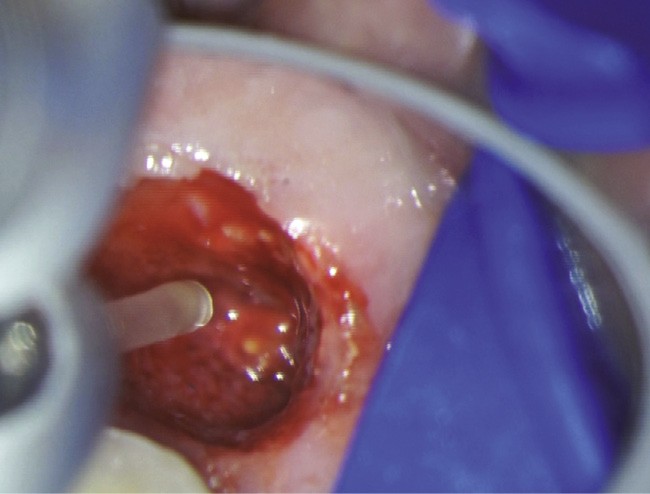

Chirurgie endodontique

L’Er:YAG a également sa place en chirurgie endodontique. En mode ablatif, il permettra l’élimination des tissus de granulation et des tissus fibro-kystiques en assurant la stérilisation de la crypte osseuse ainsi formée.

La résection apicale et la préparation a retro exposent des canaux et des tubulis dentinaires infectés, qui pourront là aussi, être décontaminés par l’action du laser Er:YAG et de l’eau distillée [36].

Les espaces non accessibles à l’instrumentation conventionnelle pourront, là aussi, être débridés et stérilisés (fig. 11a à f). Cette procédure semble accélérer de manière très significative les processus de régénération osseuse (fig. 11f).